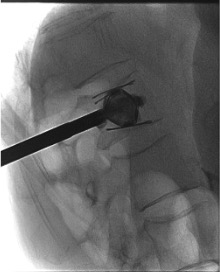

- PMMA injected through the working cannula simultaneously on both sides, filling the cavity around the in-situ implant

Simultaneous PMMA cement injection

Likely cause: Posterior cortical breach, cement injected at too low viscosity, or fracture line extending to posterior cortex.

Next step: Stop injection immediately. Wait for polymerization at leak site (1โ2 min). Resume cautiously if leak self-seals. The SpineJack implant should provide additional containment vs. vertebroplasty โ persistent posterior leak despite locked implant suggests unrecognized posterior wall compromise. Post-procedure CT mandatory.